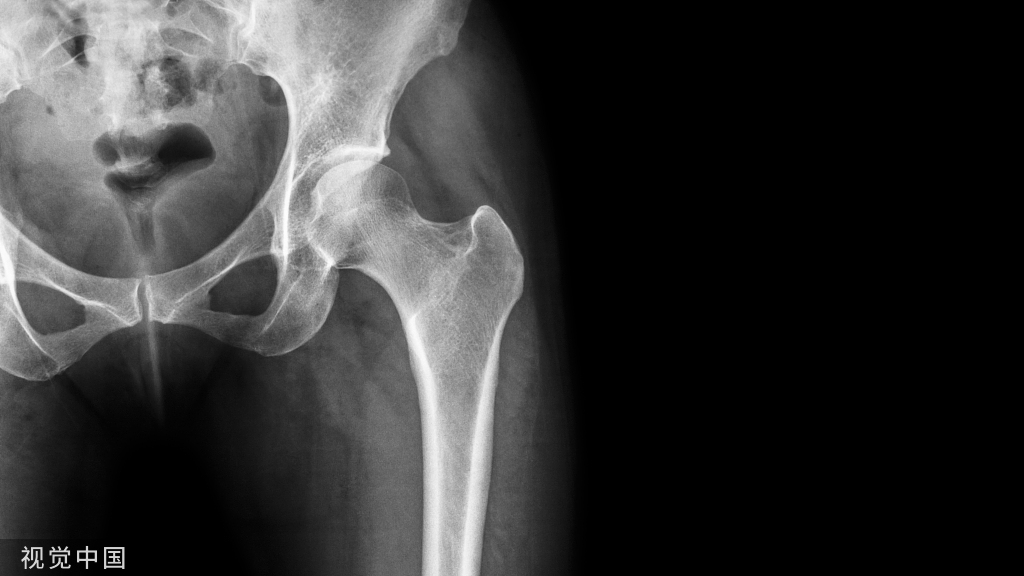

肩关节恐怖三联征的诊断

肩关节前脱位后,应注意可能合并肩袖损伤、臂丛神经损伤,特别是大于40岁的老年人。但是同时合并肩袖损伤及臂丛损伤时,明确诊断是较为困难的,两者表现出的临床症状和体征相似,且患肩伤后常肿胀、疼痛,容易导致漏诊,肩袖损伤有时会被误诊为腋神经麻痹。临床经验丰富的骨科医师在接诊肩关节前脱位患者时,会考虑到其他合并损伤的存在,并将查体与辅助检查结合运用,帮助其更好的明确诊断。患者通常以外伤后肩关节肿痛伴无法活动就诊,查体与影像学检查通常可以确诊肩关节前脱位,详细询问受伤时的情况、受伤前有无肩关节不适与活动受限的病史,如条件允许者,在肩关节复位前进行一次简单的神经血管检查,复位后再次行神经血管检查,前后对比无任何变化者,可能有神经损伤存在。Murthi等认为查体在诊断肩关节脱位的合并伤中至关重要,腋神经损伤表现为患肢无法外展、近端外侧感觉丧失;臂丛神经损伤表现为患肢远端感觉及运动丧失;冈上肌损伤表现为Jobe试验(+);冈下肌、小圆肌损伤表现为抗阻力外旋时无力;肩胛下肌损伤表现为Belly-press试验(+)、Lift-off试验(+)。Tiefenboeck等则认为腋神经位置相对较为固定的原因,容易损伤,伤后表现为三角肌下(臂章区)感觉减退。Mitchell等不建议使用三角肌力量测试检查腋神经损伤,因为在一些肩部损伤如肱骨大结节骨折、肩袖损伤后,疼痛的存在将使得全面检查更加困难。

同时,不能忽视伤后短期内随访的重要性。在急性症状缓解后,如肩关节前屈、外展、外旋无力,则应怀疑合并肩袖损伤。Toolanen等建议对于大于40岁的肩关节恐怖三联征患者伤后1周应密切随访,及时发现并明确进一步的诊断。除仔细地查体外,辅助检查也是帮助诊断的重要途径。神经损伤可以行MRI、超声、肌电图、神经传导速度等检查。肩袖损伤可以行超声、MRI、关节造影等检查。Neviaser等研究了31例肩关节前脱位后肩袖损伤的患者,建议伤后10~14d外展无力的状况如无改善,应行肩关节造影探明有无肩袖损伤。Pevny等对52例大于40岁的首次肩关节前脱位患者的回顾性研究发现,关节复位后7~10d仍有显著的疼痛和无力存在时,应行MRI或关节造影,明确是否有肩袖损伤。Ta⁃kase等建议肩关节脱位复位后,患肩持续疼痛和无力时,应行MRI查明有无合并肩袖损伤。Goubier等认为,肩关节脱位复位前后的X线片检查是不可或缺的,当存在肱骨大结节骨折时,应怀疑同时存在肩袖损伤的可能性,并行MRI明确诊断。Stayner等研究认为,对于肩关节脱位复位后2~4周仍有明显疼痛与无力症状者,应首先考虑行MRI明确有无肩袖损伤,排除肩袖损伤后应行肌电图明确有无神经损伤。Brogan等对280例创伤性臂丛神经损伤的研究发现,创伤性臂丛神经损伤伴肩袖全层撕裂者占8.2%,并认为应在制订治疗策略前评估肩袖的状态。Saab等建议肩关节脱位后可行神经传导检查,或硬膜囊成像探查有无神经损伤。Tiefenboeck等对60例肩关节脱位后臂丛神经损伤进行了一项回顾性研究,发现肌电图是一种简单便捷且廉价的检查神经损伤的方式,建议将其常规应用于临床上肩关节脱位后怀疑神经损伤的患者。由此可见,一旦发生肩关节脱位,应详细进行专科查体,做针对性影像学检查,必要时行肌电图检查,是早期诊断肩关节恐怖三联征的关键。